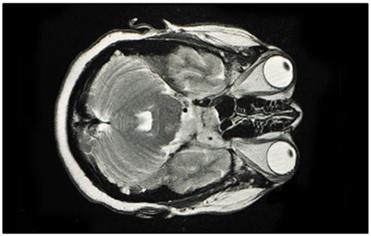

MRI stands for Magnetic Resonance Imaging. This technology relies on magnetism. It’s a more recent advancement compared to CT scans. MRI uses magnetism to create a 3D image of the body’s interior.

Similar to CT scanners, MRI machines have a moving platform. Patients lie down on this platform and are moved into a narrow cylinder. Magnets within the cylinder generate a strong magnetic field around the patient’s body. The cylinder is somewhat narrower compared to CT scanners. It’s crucial to remove all metallic objects from the body before an MRI scan. MRI scans can take around 30 minutes to complete.

Key components of an MRI scanner include: